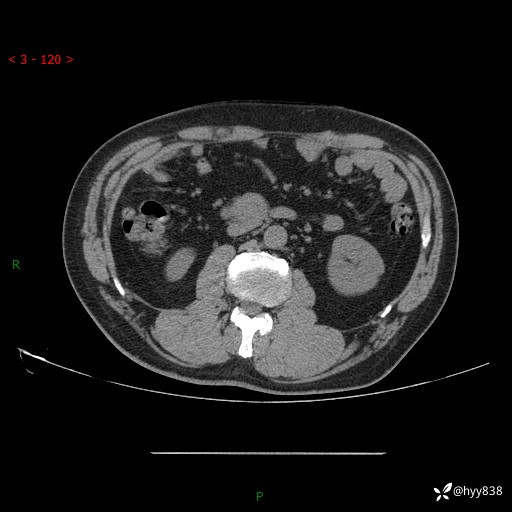

增强